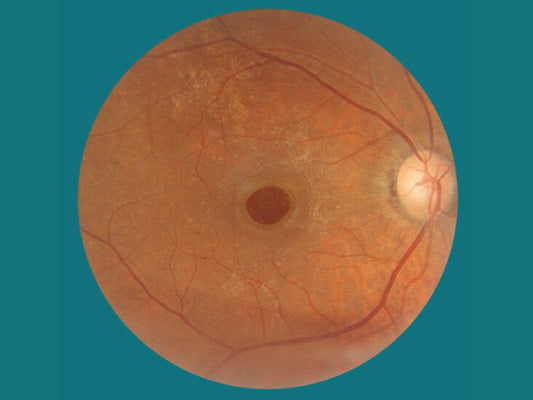

Macular hole